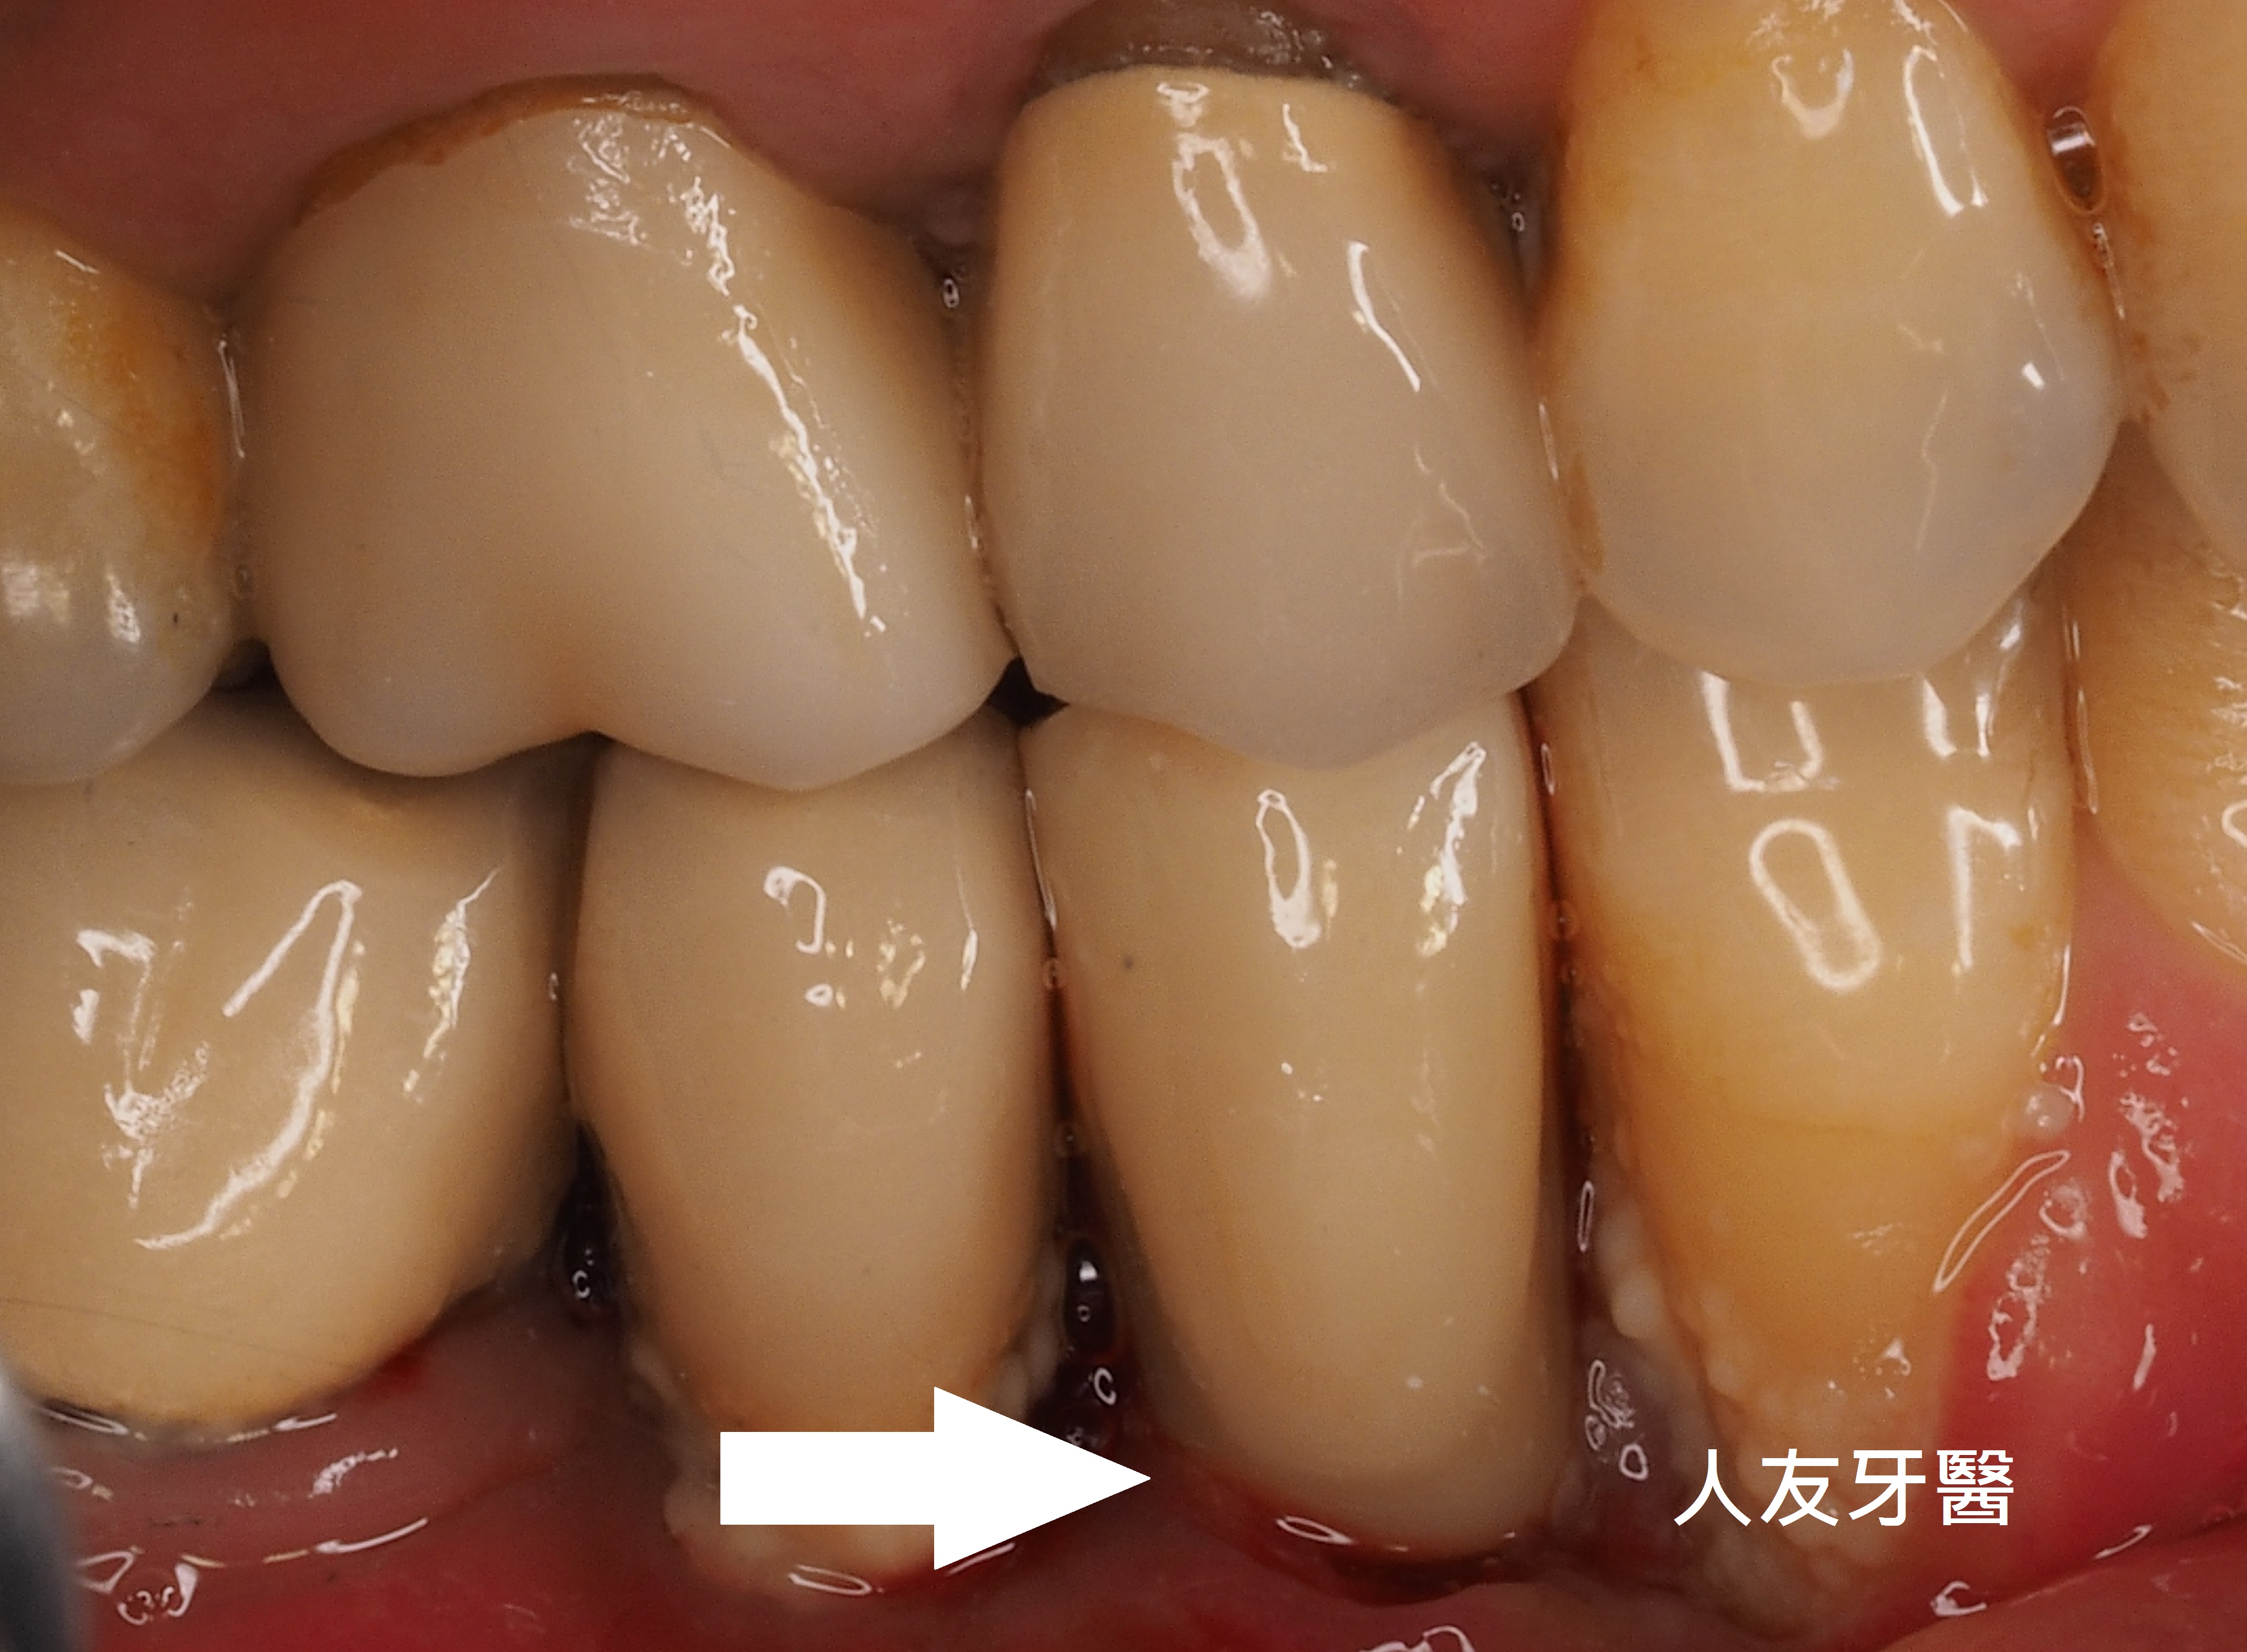

以下是牙肉生長圖片分享

上面圖片是剛完成時藍色圈圈處有明顯縫隙 上面圖片是半年後所拍攝的,藍色圈圈處牙肉已明顯生長

上圖也是剛完成時拍有明顯縫隙 上圖是半年後所拍攝藍色圈圈處已明顯牙肉生長